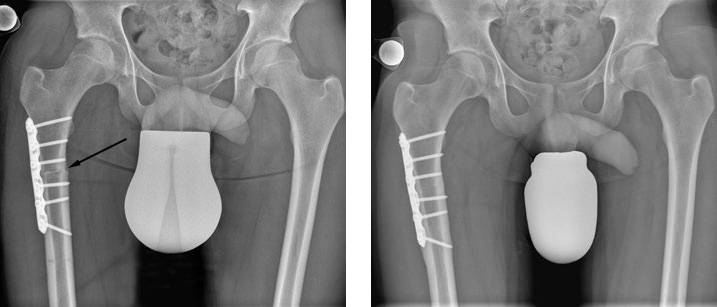

Bild: Universitätsklinik Balgrist

Der Zugang zum Oberschenkelknochen erfolgt über einen seitlichen Hautschnitt, ohne die umliegenden Muskeln zu verletzen. Der Femur wird sorgfältig unterhalb des kleinen Rollhügels (Trochanter minor) – also subtrochantär – per Schnitt getrennt und dann in den vorgeplanten Winkel gedreht. Danach wird der Knochen mittels Schrauben und einer Platte fixiert. Der Eingriff dauert ungefähr eine Stunde, je nach kombinierter Voroperation entsprechend länger.

Nach der Operation sollten Patientinnen und Patienten weniger Bewegungseinschränkungen haben und ihr Hüftgelenk sollte belastbarer und langlebiger sein. Erfahrungsgemäss ist man nach dem Eingriff beschwerdefrei. Ob und wie stark bei intensivem Sporttreiben noch Beschwerden auftreten, hängt wesentlich davon ab, wie gross die Knorpelschäden vor der Operation bereits waren. Die Platte stört manche Patientinnen und Patienten und wird deshalb nach Ausheilung des Knochens wieder entfernt. In sehr seltenen Fällen verzögert sich die Knochenheilung und/oder die Platte bricht.